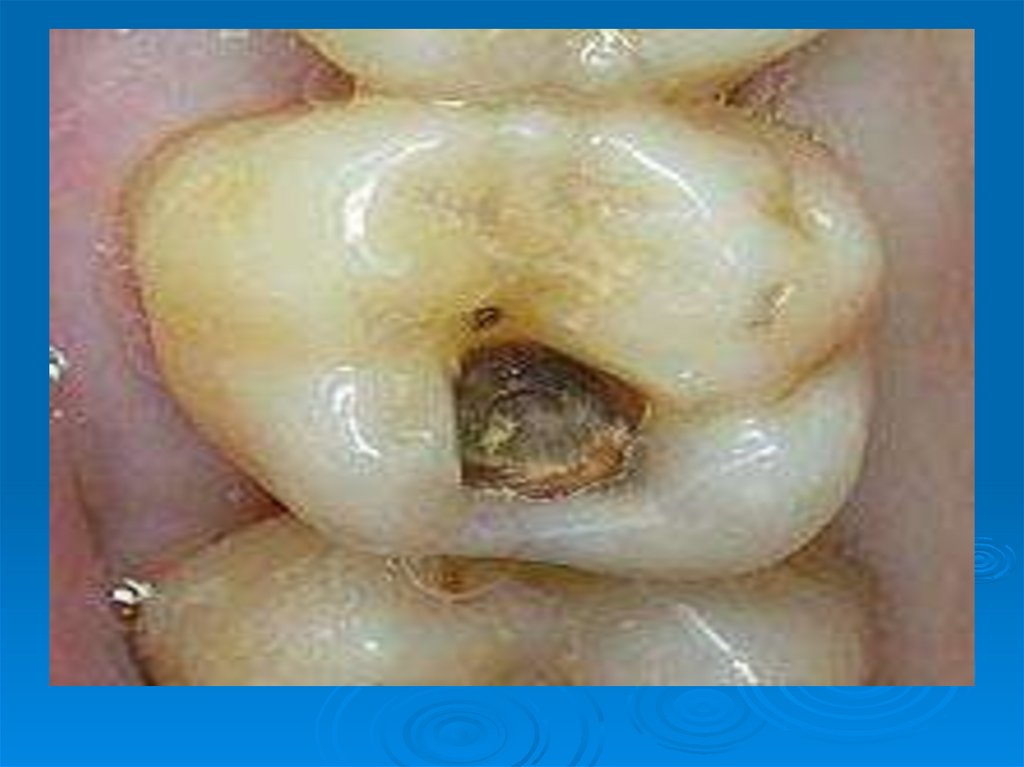

Под зубной бляшкой происходит накопление органических кислот – молочной, пировиноградной, муравьиной, масляной, пропионовой

Мягкая пища ускоряет рост зубной бляшки. Микроорганизмы зубного налета способны фиксироваться, расти на твердых тканях зуба,

13. В мягком зубном налете, имеющем пористую структуру, в результате жизнедеятельности микроорганизмов происходит накопление

продуктов их

жизнедеятельности и минеральных

солей, превращая мягкий зубной

налет в так называемую зубную

бляшку, качественно удалить

которую можно только в условиях

клиники.

14. Под зубной бляшкой происходит накопление органических кислот – молочной, пировиноградной, муравьиной, масляной, пропионовой

(продукты сбраживания углеводов), в

результате чего происходит

деминерализации участка эмали и

дальнейшее развитие кариеса. Основные

кариесогенные микроорганизмы:

Str. mutans, Str. mitis, Str salivarius,

Ведущая роль в возникновении кариеса

отводится сахарозе.